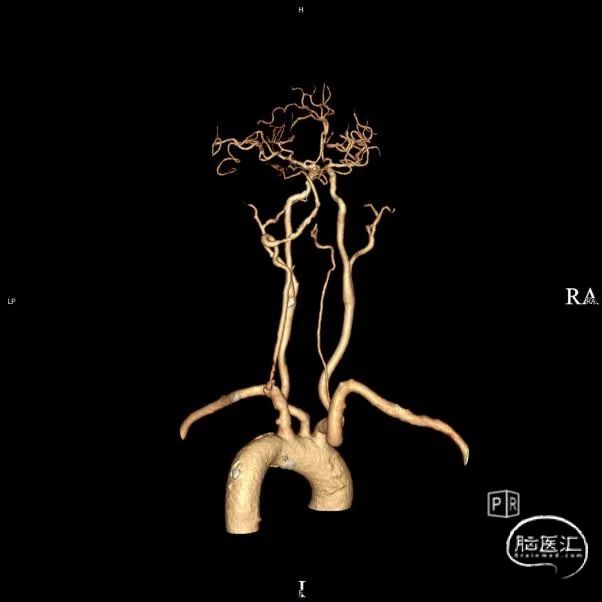

➢头颈部CTA(三维重建MIP像)

➢头颈部CTA(原始像)

患者于入院前10天突发视物重影,5分钟左右缓解,当晚18:00出现颈后不适伴左上肢持续性麻木,10天后来我院急诊神经内科就诊,就诊时测血压191/93mmHg,自行服用拜新同1粒。 完善头颅MRI:桥脑、两侧小脑急性缺血性梗塞;右侧基底节软化灶;两侧侧脑室旁少量白质疏松;老年脑改变。 入院后予药物保守并完善头颈部CTA:左侧颈内动脉虹吸段多发钙化斑块、混合斑块,管腔轻-中度狭窄,C7段小动脉瘤。右侧颈内动脉虹吸段多发钙化斑块,管腔轻度狭窄。右侧椎动脉纤细,V4段局部显示欠清。左椎V1、V2段非钙化斑块,局部管腔重度狭窄-闭塞,V4段钙化斑块,管腔中度狭窄。右侧部分型大脑后动脉,P1段重度狭窄,P2段中度狭窄。双侧大脑中动脉M2段中至重度狭窄。 告知患者病情存在进一步进展可能,患者家属商量后要求手术治疗。

术前影像考虑右侧孤立椎,左侧椎动脉V1段重度狭窄、狭窄段以远扭曲成襻且合并长节段多发动脉粥样硬化狭窄改变(夹层待排),同时左椎V4段局部重度狭窄可能;